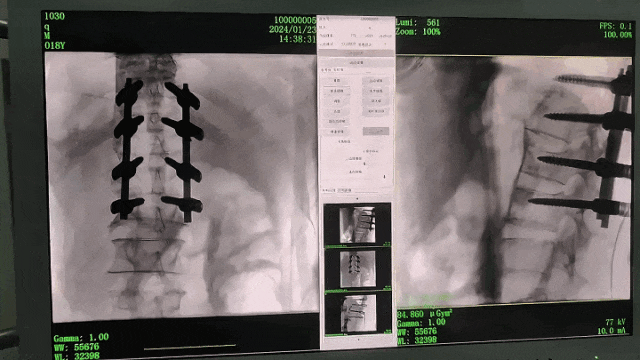

Compared with the traditional 21CM×21CM imaging size, Perlove's large flat-panel integrated C-arm has a larger imaging size of 30CM×30CM, capable of imaging 5.5 vertebrae at a time, presenting more comprehensive image information, even for young surgeons with little surgical experience, they can quickly determine the vertebral body segments and locate the surgical site through the image, avoiding multiple localization due to the insufficient field of view, Repeated exposure, improve efficiency and avoid excessive intake of radiation at the same time.

Comparison of Perlove's IntegratedLarge FPD C-Arm Images with Traditional Images

Note: The blue dotted line is the imaging area of the traditional 21CM×21CM flat panel.